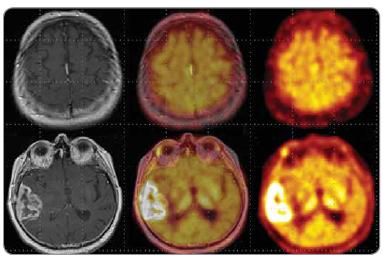

Od pozitronové emisní tomografie se v neuroonkologii požaduje odlišit benigní a maligní léze mozku, stanovit grading nádorů, určit nejvhodnější místo pro biopsii, tzv. PET-em navigovaná stereotaktická biopsie, stanovit reziduum nádoru po terapii, zjistit rekurenci nádoru, zjistit metastatické postižení mozku. Za tímto účelem je pro PET vyšetření mozku mimo 18F-fluoro-deoxy-glukózu (FDG), která tvoří základní radiofarmakum využívané pro vyšetření mozku, teoreticky možné využít množství různých neaktivních nosičů značených pozitronovými zářiči připravených v cyklotronu (18F, 11C, 13N,15O) nebo tzv. generátorových zářičů (68Ga, 82Rb). Většina non-FDG radiofarmak se však vzhledem k problémům souvisejícím s výrobou, distribucí nebo cenou využívají jenom v omezené míře, zejména v rámci výzkumných projektů. Mimo FDG se z alternativních radiofarmak v PET Centru Masarykova onkologického ústavu v Brně používají 18F- fluorothymidin a 11C-methionin. 18F-flurothymidin (FLT) je aktivně transportován TK1 v S-fázi mitotického cyklu a akumulace tohoto radiofarmaka koreluje oproti FDG s markerem proliferační aktivity Ki-67. FLT se v gliomech akumuluje cca 3krát méně než FDG, tumor/background ratio je však u FLT, vzhledem k minimální mitotické aktivitě ve zdravé mozkové tkáni, cca 3krát vyšší než u FDG. 11C-methionin ( MET) vykazuje výrazně vyšší akumulaci v lézích se zvýšenou proteosyntézou a vyšší vaskulární permeabilitou. Jeho výhodou je relativně nižší fyziologická akumulace v mozku ve srovnání s FDG. Potenciální využití tohoto radiofarmaka vidíme pro grading tumorů, zjištění relapsu po operaci nebo radioterapii, využití u stereotaktické biopsii a plánování radioterapie. Využití MET je omezené pro PET centra disponující ve své blízkosti cyklotronem, protože vzhledem ke krátkému fyzikálnímu poločasu 11C (20 min) není možné radiofarmaka značená 11C distribuovat na větší vzdálenost.